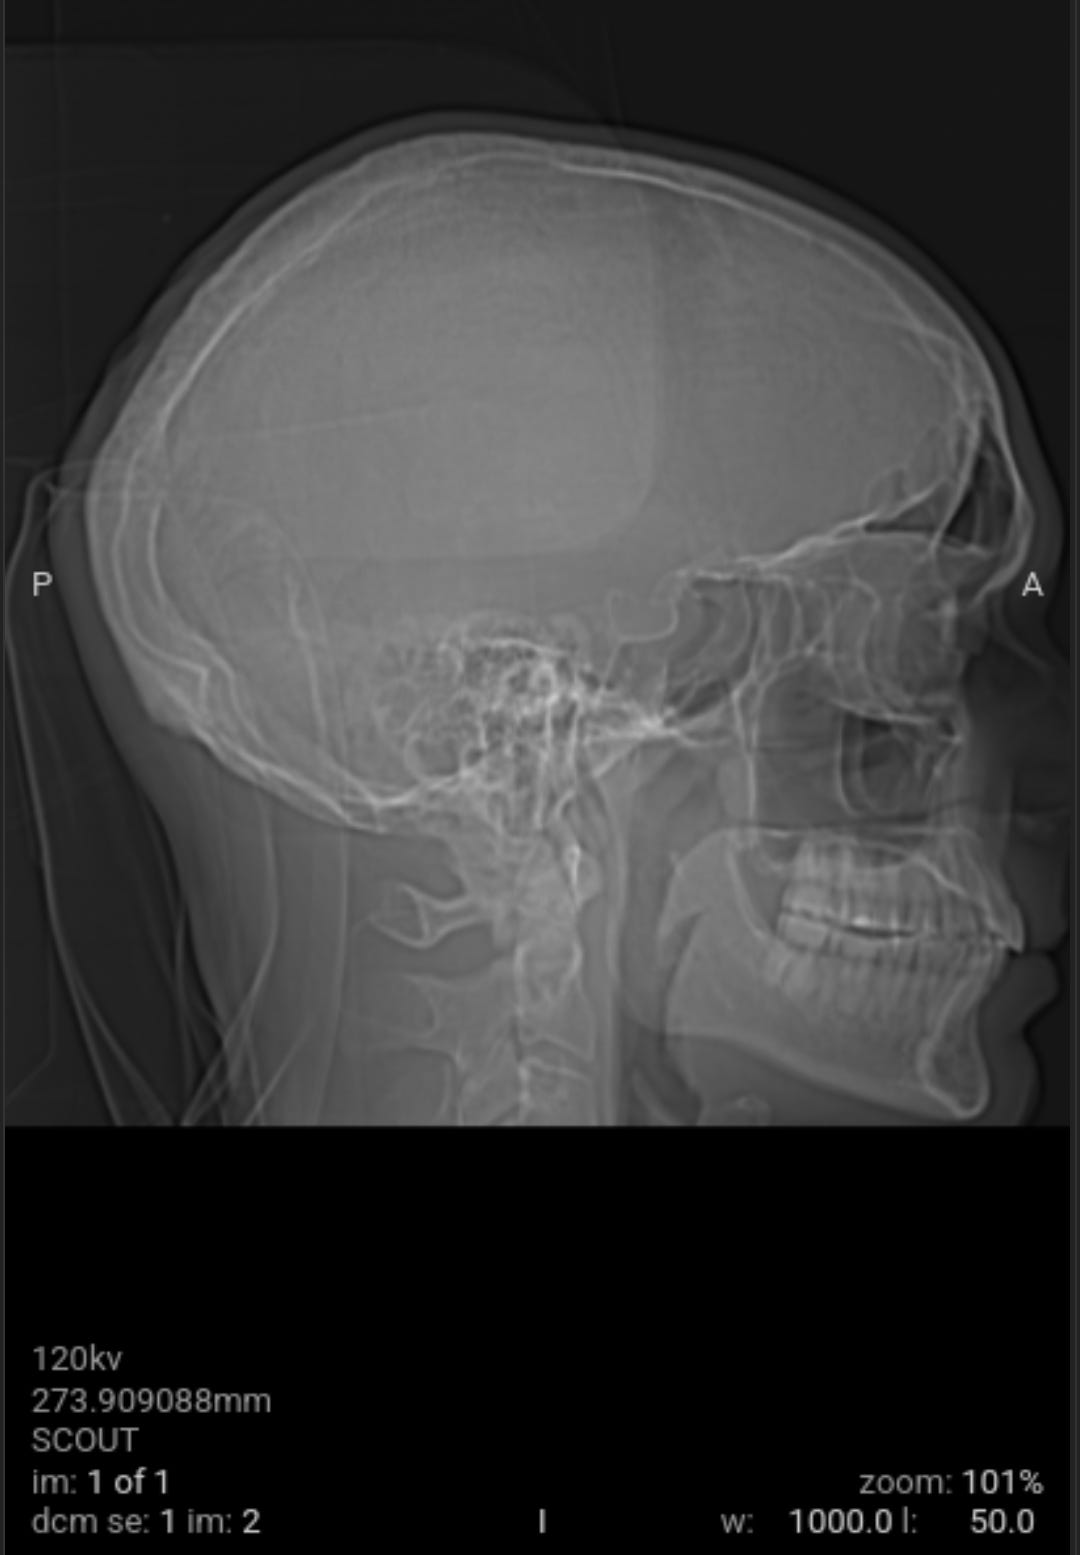

As a followup to eliminate all possible and probably causes of the weaponized audio-video-communications and pathogen nanotechnology. Got blood work and CAT scan done. Results came back good.

As a followup to eliminate all possible and probably causes of the weaponized audio-video-communications CNT and pathogen nanotechnology WPT, I got blood work and CAT scan done yesterday. All came back good with the exception of a low Red Blood Cell RBC count due to my cleansing diet on vegetables and plant based proteins that needs more iron in it with vitamin C, I already dose with vitamin B12 (preference is methylcobalamine). The medical staff could not determine what the unknown material removed from my body was from the salt baths or the material that moved around and itches at times on the left side of my head.

The void spaces on left side are what I suspect to be where the nanotechnology circuitry was removed by magnetic vortex skyrmion unit, chelators, salt water baths, no yeast diet and no added sugar diet. Note the scans do not show any nanotechnology based synthetic biology parasites. This is why the samples pulled from my body were classified as unknown by the western medical staff not trained in the nanotechnology and synthetic biology knowledge domain, a huge gap in Western medicine.